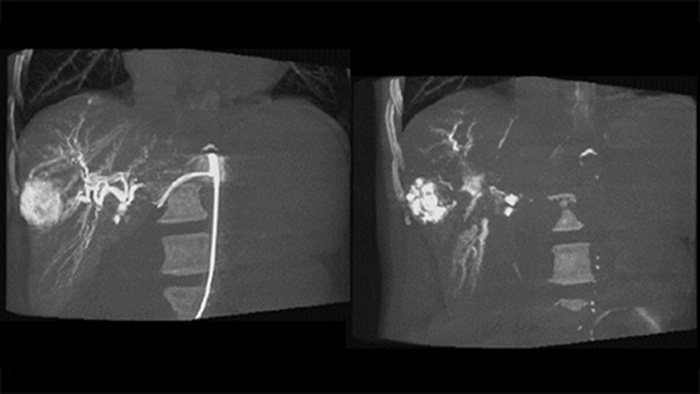

Chemo-/Radioembolisationsverfahren wie TACE und SIRT erfordern eine höhere Standardisierung und Effizienz. Die Tumore müssen jedes Mal zuverlässig und konsistent lokalisiert, alle Versorgungsgefäße erkannt und die geeigneten interventionellen Maßnahmen geplant und durchgeführt werden. Unsere dedizierte Lösung kann die Erkennung von Versorgungsgefäßen im Vergleich zur alleinigen Verwendung von Cone-Beam-CT signifikant verbessern. Für möglichst effiziente TACE-Verfahren kann EmboGuide die Empfindlichkeit verbessern, falsch positive Ergebnisse reduzieren und eine höhere Konsistenz zwischen den befundenden Medizinern gewährleisten.1

Unsere dedizierte Lösung verbessert die Erkennung von Versorgungsgefäßen signifikant. Mit EmboGuide können Sie die Effizienz Ihrer TACE-Verfahren maximieren, da die Funktion die Empfindlichkeit verbessert, falsch positive Ergebnisse reduziert und eine höhere Konsistenz zwischen den befundenden Medizinern ermöglicht.1 Darüber hinaus bietet EmboGuide eine Arbeitsablauf-basierte Live-3D-Führung mit automatischer Erkennung der Versorgungsgefäße1.

Dual View ermöglicht die gleichzeitige Darstellung von zwei CBCT-Datensätzen. Sowohl die arterielle als auch die postarterielle Phase können nebeneinander oder in einer fusionierten Überlagerungsansicht angezeigt werden.

Dual View ermöglicht die gleichzeitige Darstellung eines 3D-Bildes der arteriellen Phase vor der Embolisation und eines Bildes nach der Embolisation zur Bestimmung des Behandlungsendpunkts.